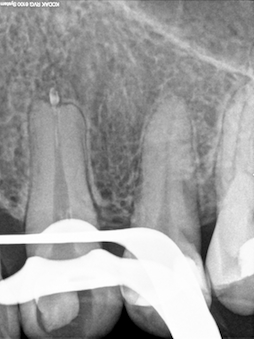

Veröffentlicht 2. Dezember 2008 am 254 × 339 in Thermafil – Revision (2)

Fremdkörperkontrolle

Fremdkörper periapikal